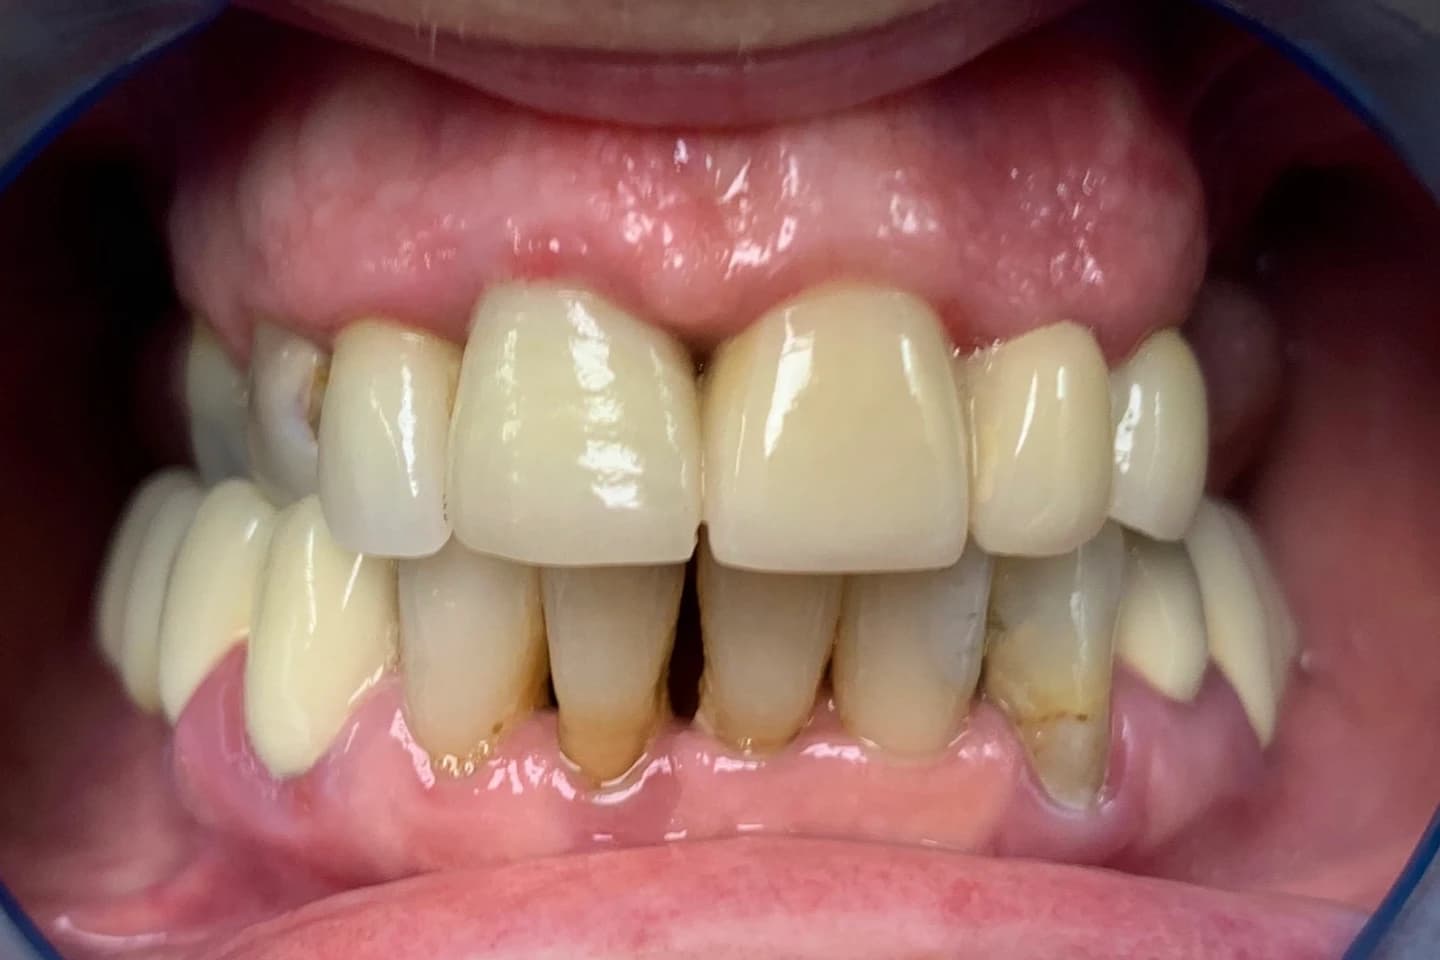

Pogledajte našu galeriju radova i utiske mnogobrojnih zadovoljnih pacijenata! U ordinaciji Marco Dental Tourism verujemo da osmeh može promeniti sve. Želimo da vam pomognemo da postignete osmeh o kom ste oduvek sanjali. Poslušajte inspirativne priče o transformaciji osmeha naših pacijenata, zajedno sa slikama pre i posle početka lečenja, koje govore više od reči.

Stomatološka ordinacija Marco Dental Tourism svakodnevno stvara neverovatne transformacije osmeha. Pogledajte galeriju naših radova i uverite se u moć stomatologije!

Želimo i vama da pomognemo da postignete savrršen osmeh kada su u pitanju položaj i oblici zuba. Zato smo prikupili inspirativne priče i fotografije zuba naših pacijenata, koje će vam pokazati šta je sve moguće uz stručnost i posvećenost našeg tima.